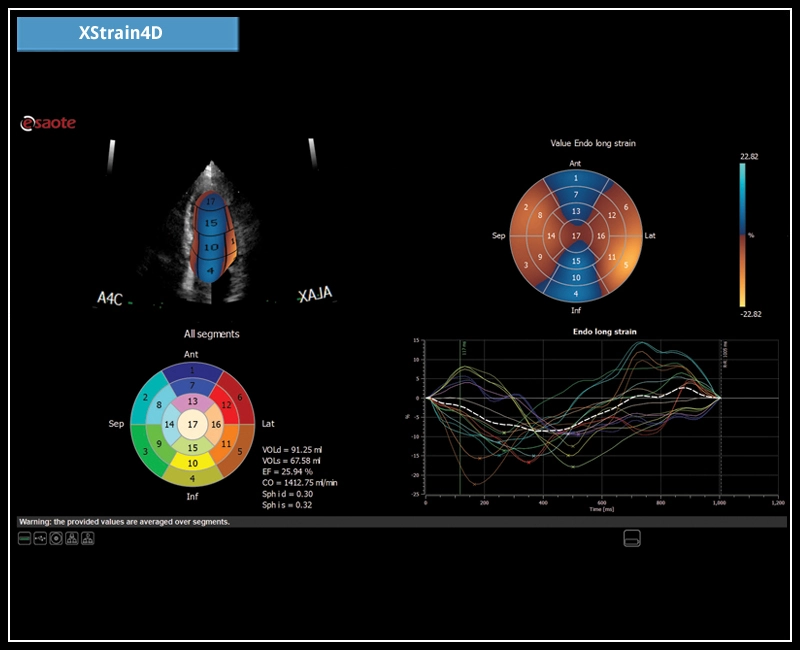

MyLab™X7 - XStrain4D

MyLab™X7 - XStrain4D